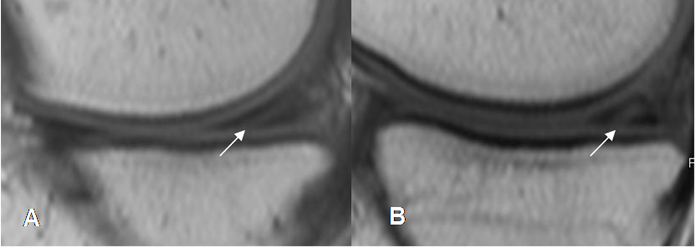

Fig 74. Ruptura meniscal oblicua.

A: RM sagital en T1 y B: RM sagital en STIR. Imagen en sentido oblicuo, que se comunica con la superficie articular inferior, por ruptura meniscal.